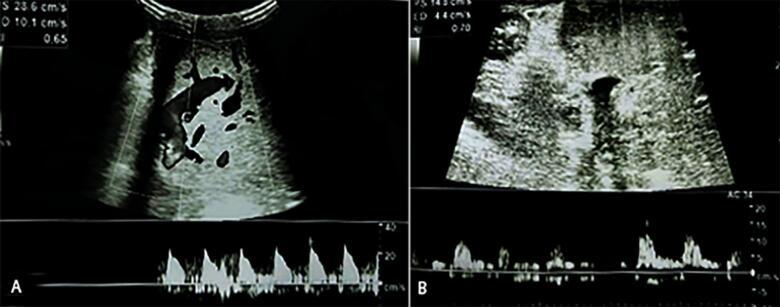

一名13个月大的患有胆道闭锁且已接受葛西手术的婴儿接受了活体供肝肝移植。术后第9天,多普勒超声检测到即将发生肝动脉血栓形成的迹象,计算机断层血管造影证实了这一情况。患者接受了剂量为0.3毫克/千克/小时的静脉注射阿替普酶治疗。输注3.5小时后,多普勒超声显示肝动脉血流改善。由于腹腔内出血,输注提前停止,对出血进行了保守处理。患者未进行手术干预病情稳定,术后第32天出院,肝动脉血流稳定。在6个月的随访中,肝动脉保持通畅,患者临床状况稳定。